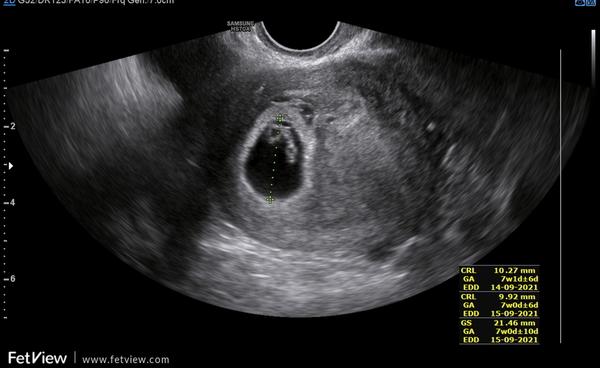

Ahoj holky, byla jsem na UZ, jsem 7+6,a ale na UZ jsem byla 7+-1(3) Srdeční akce tam byla, ale ještě ji neměřili. Kdy jste holky poprvé slyšely srdeční akci a ne jen viděli. Plus je náš prcek nějaký menší než má být, tak snad bude vše ok. Mám jen strach. Poraďte prosím

Je to moje první mimi, tak mám strach :/ Snad bude vše v pořádku, hlavně že srdíčko tam je a ma akci, jen jestě není slyšet.

Tak holky dnes jsem slyšela srdíčko! Bylo to krásný, jak je to moje první těhotenství, tak slyšet srdce někoho tak malého, ale tak silného, je neuvěřitelné! Moc děkuji za všechny zprávy, už nás s prckem čekají odběry, tak snad bude vše ok a mám datum prvního screeningu. Hradila ho u vás pojištovna nebo ne?